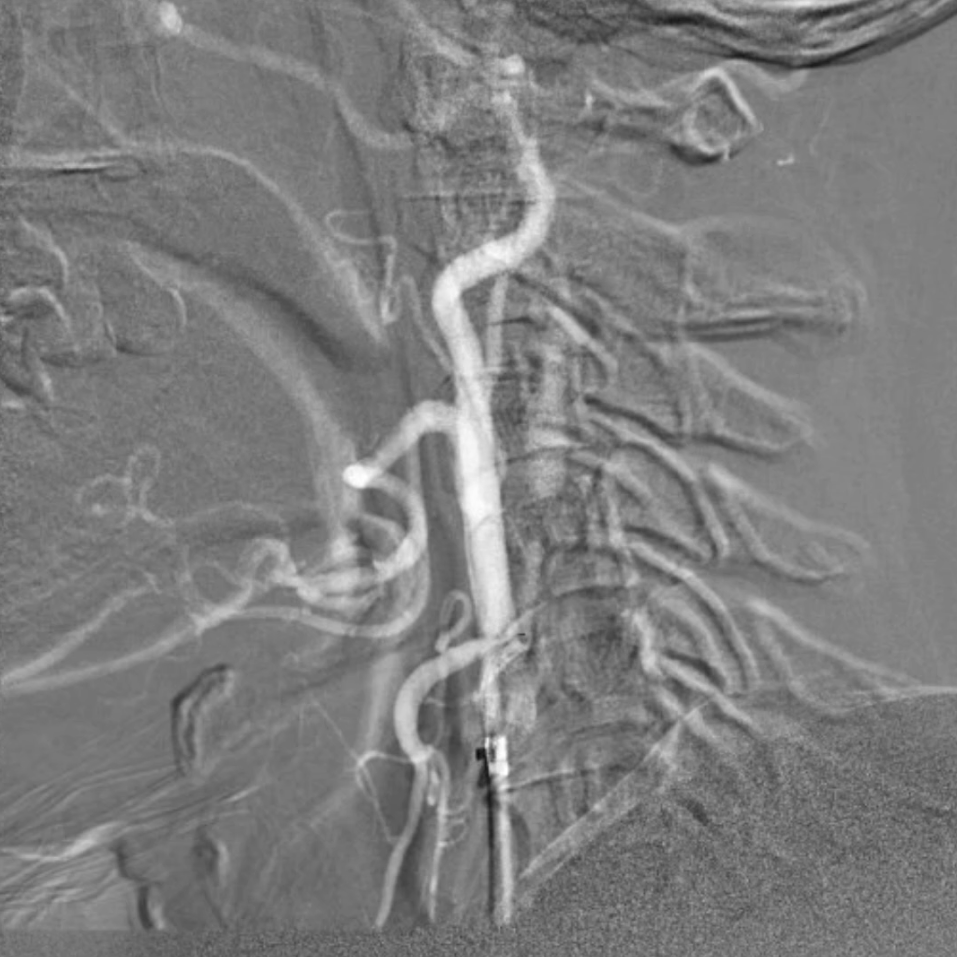

术后评估

血供改善与安全性验证

造影显示:支架膨胀良好,无需后扩张;

颅内血供:左侧颈内动脉血流通畅,因右侧闭塞,左侧成为全脑主要供血通路,血供恢复满意